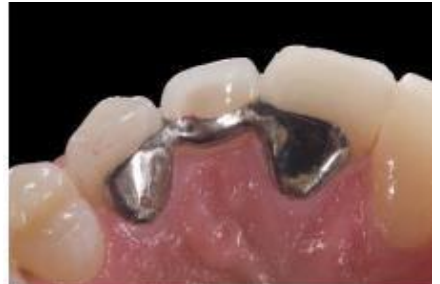

MFD EXAMS /23 6 1234567891011121314151617181920212223 You have 30 min to complete this exam. The timer will start once you begin Attention: Only a few minutes left! Please submit your answers soon. MFD 1 Get a quick sneak peek before the real exam !This trial quiz is designed to show you the question style, difficulty level, and how the options will appear on the platform. 1 / 23 1. What is the lethal dose and toxic dose of fluoride, management? Check 2 / 23 2. What the advantage of silver diamine over other methods and disadvantages ? Check 3 / 23 3. Method of topical fluoride application with concentration ? Check 4 / 23 4. What will happen if left untreated? Check 5 / 23 5. What changes that will happen if the habit stopped? Check 6 / 23 6. Give 3 of your initial stage of treatment? Check 7 / 23 7. What are the causes? Check 8 / 23 8. What is this? Check 9 / 23 9. Then they specified the type of pain and asked about the diagnosis Check 10 / 23 10. What other tests to check vitality of the pulp? Check 11 / 23 11. What are the factors will govern the Rx of Posterior cross bite ? Check 12 / 23 12. What are the factors that govern the treatment of anterior cross bite? Check 13 / 23 13. Name the appliance that you can use to treat this case? Check 14 / 23 14. Name 3 causes? Check 15 / 23 15. Name the most important clinical diagnostic information you need to know. (check RCSI intensive course )? Check 16 / 23 16. What do you see? Check 17 / 23 17. What is your treatment? Check 18 / 23 18. Name the investigations needed? Check 19 / 23 19. causes for gingival enlargement ? Check 20 / 23 20. What is the common side effect of this drug? Check 21 / 23 21. Name the drug that he may take to treat this condition? Check 22 / 23 22. The patient may have what? Check 23 / 23 23. What is this clinical condition? Check /31 2 12345678910111213141516171819202122232425262728293031 You have 30 min to complete this exam. The timer will start once you begin Attention: Only a few minutes left! Please submit your answers soon. MFD 2 Get a quick sneak peek before the real exam !This trial quiz is designed to show you the question style, difficulty level, and how the options will appear on the platform. 1 / 31 1. Mention 2 fixed space maintainers and 2 removable space maintainers other from mentioned : Check 2 / 31 2. Other space maintenance used for child lost primary second molar E before the eruption of the permanent molars ? Check 3 / 31 3. What are the difference between nance appliance and Transpalatal arch Check 4 / 31 4. What material used to attach band? Check 5 / 31 5. What instruction you give to patient? Check 6 / 31 6. Name other fixed space maintainer used in upper jaw and mechanism of their action? Check 7 / 31 7. What component of this appliance? Check 8 / 31 8. What is this appliance , for what its used ? Check 9 / 31 9. Treatment? Check 10 / 31 10. Define Abrasion and Erosion? Check 11 / 31 11. What does this picture show? Check 12 / 31 12. what investigations you can do ? Check 13 / 31 13. Drugs can lead to lichenoid reaction Check 14 / 31 14. What extra oral features in “ Lichenoid reaction )? Check 15 / 31 15. What microscopical features of it ( licheonoid reaction )? Check 16 / 31 16. Definitive diagnosis ? Check 17 / 31 17. Mention type of suggested biopsy ? Check 18 / 31 18. Mention 4 differential diagnosis ? Check 19 / 31 19. Mention 4 questions you will ask the patient ? Check 20 / 31 20. Give 4 intraoral decription of what you see ? Check 21 / 31 21. What the other surgery can be performed to make prothesis? Check 22 / 31 22. Can this tooth stand with fixed prothesis? (in the opg )à taken from Malek file ? Check 23 / 31 23. Radiograph of missing multiple teeth consider it according to Antes law? ON which tooth you will make Abutment ? Check 24 / 31 24. What is Antes law? Check 25 / 31 25. What is best one to use as abutment in fixed prosthesis A or B? Check 26 / 31 26. What relevance of this picture? Check 27 / 31 27. What’s complication of doing surgery in this area floor of mouth? Check 28 / 31 28. Other 2 radiograph needed in diagnosis? Check 29 / 31 29. Give 4 differential diagnosis? Check 30 / 31 30. What can you see ? Check 31 / 31 31. What is the name of radiograph? Check Your score is /30 1 123456789101112131415161718192021222324252627282930 You have 30 min to complete this exam. The timer will start once you begin Attention: Only a few minutes left! Please submit your answers soon. MFD 3 Get a quick sneak peek before the real exam !This trial quiz is designed to show you the question style, difficulty level, and how the options will appear on the platform. 1 / 30 1. Treatment? Check 2 / 30 2. Histopathology? Check 3 / 30 3. Differential diagnosis Check 4 / 30 4. Clinical features’? Check 5 / 30 5. Patient said, this lesion is very frequent, why? Check 6 / 30 6. What are the causes for ulcers? Check 7 / 30 7. Patient have other signs like uveitis ,Genital ulcerations which syndrome he had ? Check 8 / 30 8. Name of the lesion ? Check 9 / 30 9. Mention some TMJ movement ? Check 10 / 30 10. Blood supply ? Check 11 / 30 11. Nerve supply ? Check 12 / 30 12. Which muscles close? Check 13 / 30 13. Action of open and open wide? Check 14 / 30 14. Why it’s Atypical joint ? Check 15 / 30 15. Name of the ligaments ? Check 16 / 30 16. What would be your management? Check 17 / 30 17. Bacteria involved Check 18 / 30 18. Which type of Periodontitis? Check 19 / 30 19. Treatment? Check 20 / 30 20. Histopathology? Check 21 / 30 21. Differential diagnosis? Check 22 / 30 22. Clinical features? Check 23 / 30 23. What are the time frames for making a complaint? Check 24 / 30 24. What are the 3 points related to negligence? Check 25 / 30 25. Who is allowed access to the patient records? Check 26 / 30 26. How to differentiate if it is upper or lower motor neuron lesion? Check 27 / 30 27. Management? Check 28 / 30 28. What are the causes? Check 29 / 30 29. What should you advise the patient to do? Check 30 / 30 30. What is this lesion? Check Your score is /24 1 123456789101112131415161718192021222324 You have 30 min to complete this exam. The timer will start once you begin Attention: Only a few minutes left! Please submit your answers soon. MFD 4 Get a quick sneak peek before the real exam !This trial quiz is designed to show you the question style, difficulty level, and how the options will appear on the platform. 1 / 24 1. What does MRONJ stands for? Check 2 / 24 2. Give definition for MRONJ Check 3 / 24 3. For what medical problems these medications are used? Check 4 / 24 4. Stages of MRONJ 3 Check 5 / 24 5. What’s this appliance? Check 6 / 24 6. At what age is it used? Check 7 / 24 7. What type of malocclusion is it used to treat? Check 8 / 24 8. What changes will produce? (4 options) Check 9 / 24 9. Disadvantages? Check 10 / 24 10. Why is it flabby tissue? Check 11 / 24 11. what is this condition called? Check 12 / 24 12. Causes ? Check 13 / 24 13. Clinical Features ? Check 14 / 24 14. How to avoid it ? Check 15 / 24 15. Management? Check 16 / 24 16. Ideal post length and width Check 17 / 24 17. Definition of Ferrule it’s the Check 18 / 24 18. What is the importance of the ferrule effect ? Check 19 / 24 19. Describe the radiolucency? Check 20 / 24 20. Give 6 differential diagnosis? Check 21 / 24 21. Give 5 radiographical features? Check 22 / 24 22. What is the difference between incisional and excisional biopsy? Check 23 / 24 23. What other 2 plain radiographs we can we can take? Check 24 / 24 24. ALARA? Check Your score is /22 1 12345678910111213141516171819202122 You have 30 min to complete this exam. The timer will start once you begin Attention: Only a few minutes left! Please submit your answers soon. MFD 5 Get a quick sneak peek before the real exam !This trial quiz is designed to show you the question style, difficulty level, and how the options will appear on the platform. 1 / 22 1. . Types of external root resorption? Check 2 / 22 2. The cause of root resorption in the pic? Check 3 / 22 3. How you will treat it? Check 4 / 22 4. What is this probe? Check 5 / 22 5. What is the mark a ? Check 6 / 22 6. What is the mark b ? Check 7 / 22 7. What is the score from the given reading? Check 8 / 22 8. What is the treatment need of the patient according to the score? Check 9 / 22 9. What is the differential diagnosis ? Check 10 / 22 10. Four clinical features of the lesion? Check 11 / 22 11. Treatment ? Check 12 / 22 12. Describe what do you see? Check 13 / 22 13. Causes for it ? Check 14 / 22 14. Treatment ? Check 15 / 22 15. Picture of patient with Anaphylaxis…after taking Check 16 / 22 16. What is diagnosis? - Check 17 / 22 17. What a the signs of Anaphyalxis reactions ? Check 18 / 22 18. What first line of treatment? Dose? Route of Adminstration? Check 19 / 22 19. Other drug used? Check 20 / 22 20. What are expected complications if not treated ? Check 21 / 22 21. What precautions should be made to prevent anaphylaxis reaction ? - Check 22 / 22 22. Name 10 drug in emergency used with their route of Administration and their condition they use in? Check Your score is /36 1 123456789101112131415161718192021222324252627282930313233343536 You have 30 min to complete this exam. The timer will start once you begin Attention: Only a few minutes left! Please submit your answers soon. MFD 6 Get a quick sneak peek before the real exam !This trial quiz is designed to show you the question style, difficulty level, and how the options will appear on the platform. 1 / 36 1. . What are cases that you have to extract the primary tooth? Check 2 / 36 2. D. What are the indications for extraction? Check 3 / 36 3. What are your treatment options? Check 4 / 36 4. Investigations? Check 5 / 36 5. Type of trauma? Check 6 / 36 6. Patient diagnosed with sjorgen syndrome Histology ? - Check 7 / 36 7. Patient diagnosed with sjorgen syndrome Mention four blood investigations ? Check 8 / 36 8. Patient diagnosed with sjorgen syndrome Mention two sites where can we take the biopsy Check 9 / 36 9. Patient diagnosed with sjorgen syndrome How can you differentiate between primary and secondary ? Check 10 / 36 10. Gingival inflammation present in which syndrome Check 11 / 36 11. What is the treatment? Check 12 / 36 12. mention another connective tissue disease that can lead to lesions “ intraorally “ similar to the Lichen planus ? Check 13 / 36 13. what serious complication can arise from Erosive lichen planus ? Check 14 / 36 14. If it was atrophic lesion what histology might be seen ? Check 15 / 36 15. List the histological features of lichen planus ? Check 16 / 36 16. Lichen planus what dose it affect? Check 17 / 36 17. Age group commonly affected ? -ref SAQ Check 18 / 36 18. What are the clinical presentation ‘ types of lichen planus ‘ Check 19 / 36 19. What might you see in patient’s body that has a relation to this lesion? Check 20 / 36 20. What are the differential diagnoses? Check 21 / 36 21. Factors for platelet adhesion? Check 22 / 36 22. What can you see? Check 23 / 36 23. Other 2 process of hemostasis? Check 24 / 36 24. Two diseases in which they increase ? Check 25 / 36 25. Two diseases in which they decrease? Check 26 / 36 26. Medical term when they decrease? And if they increased Check 27 / 36 27. Function Check 28 / 36 28. Life span ? Check 29 / 36 29. From where they arise? Check 30 / 36 30. Normal number? Check 31 / 36 31. What are the function of the guiding plane ? Check 32 / 36 32. The success rate ? Check 33 / 36 33. Mention single extra preparation requirement for Resin bonded bridge in posterior teeth ? Check 34 / 36 34. Mention 5 preparation features of it? Check 35 / 36 35. Give two advantages of it ? Check 36 / 36 36. What’s the name of this prosthesis? Check Your score is /23 1 1234567891011121314151617181920212223 You have 30 min to complete this exam. The timer will start once you begin Attention: Only a few minutes left! Please submit your answers soon. MFD 7 Get a quick sneak peek before the real exam !This trial quiz is designed to show you the question style, difficulty level, and how the options will appear on the platform. 1 / 23 1. If the same scenario but the tooth is subluxated. What is the management? Check 2 / 23 2. Aim of this procedure Check 3 / 23 3. Steps to do this procedure? Check 4 / 23 4. Management? How to asses the vitality of the tooth Check 5 / 23 5. Mention factors that can affect the treatment plan ? Check 6 / 23 6. Identify the Kenneyd’s classification Check 7 / 23 7. Name its parts? Check 8 / 23 8. Uses of Surveyor Check 9 / 23 9. What is this ? Check 10 / 23 10. Criteria for hand piece sterilization Check 11 / 23 11. steps for wrapped instrument sterilization process ( ref : sterilization in SDCEP)? Check 12 / 23 12. What is the difference between sterilization and decontamination? Check 13 / 23 13. Optimal temperature & pressure & time for autoclave? Check 14 / 23 14. Difference between vacuum and non-vacuum autoclave in mechanism? Check 15 / 23 15. Optimum temperature? Check 16 / 23 16. Advantage of vaccum over non vaccum? Check 17 / 23 17. What is the significance of forehead wrinkling? Check 18 / 23 18. What is Ramsy haunt syndrome ? Rx ? and is it LMN or UMN ? Check 19 / 23 19. Enumerate 3 extracranial and intracranial causes for this ? Check 20 / 23 20. What are the branches of facial nerve? Check 21 / 23 21. Why do we suture the eye in a patient with Facial Palsy? Check 22 / 23 22. Differentiate between Upper and Lower Motor Neuron lesions? Check 23 / 23 23. What is shown in photograph? Check Your score is /27 0 123456789101112131415161718192021222324252627 You have 30 min to complete this exam. The timer will start once you begin Attention: Only a few minutes left! Please submit your answers soon. MFD 8 Get a quick sneak peek before the real exam !This trial quiz is designed to show you the question style, difficulty level, and how the options will appear on the platform. 1 / 27 1. Mention 4 diseases you would see in HIV Patients? Check 2 / 27 2. Give 2 differential diagnosis for this lesion? Check 3 / 27 3. Describe the lesion shown in Photograph B? Check 4 / 27 4. What is your diagnosis ? Check 5 / 27 5. Describe the lesion shown in Photograph A? Check 6 / 27 6. Disadvantages of gold ? Check 7 / 27 7. Ideal cement for All Porcelain? Check 8 / 27 8. Which cement would u use for high caries risk patient? Check 9 / 27 9. How much would you prepare for functional and non-functional cusps in Gold Crown? Check 10 / 27 10. what crown would you go for in bruxism patients out of these 3? Check 11 / 27 11. Name the 3 restorations? Check 12 / 27 12. After administering Local Anesthesia and deciding the choice of biopsy. What should be done before biopsying the lesion? Check 13 / 27 13. Name 2 systemic steroids with dosage you would recommend for this patient? Check 14 / 27 14. Name 2 topical steroids with dosage you would recommend for this patient? Check 15 / 27 15. What is your diagnosis? Check 16 / 27 16. Describe the lesion shown in photograph? Check 17 / 27 17. Name 5 options to increase retention and stability in class l Check 18 / 27 18. E. What is the function of the RPI system ? Check 19 / 27 19. What are the 2 disadvantages of the 2 restorations you mentioned? Check 20 / 27 20. What materials are your 2 restorations made of? Check 21 / 27 21. Other than implants what restoration would you place in this patient? Check 22 / 27 22. Which Kennedy’s classification is this? Check 23 / 27 23. Describe your management? Check 24 / 27 24. What may be the patient complaint? Check 25 / 27 25. What are the causes of this? Check 26 / 27 26. Describe what you see in the photograph? Check 27 / 27 27. which 4 examinations would you undertake? Check Your score is /31 0 12345678910111213141516171819202122232425262728293031 You have 30 min to complete this exam. The timer will start once you begin Attention: Only a few minutes left! Please submit your answers soon. MFD 9 Get a quick sneak peek before the real exam !This trial quiz is designed to show you the question style, difficulty level, and how the options will appear on the platform. 1 / 31 1. Describe what you see in the photograph? Check 2 / 31 2. Three other features of this syndrome ? Check 3 / 31 3. What is the medical condition associated with it “? Multiple OKC? Check 4 / 31 4. Where expansion occurs in the OKC ? Check 5 / 31 5. From which cells this lesion arises from? Check 6 / 31 6. What is your diagnosis? Check 7 / 31 7. What is the histopathology of the lesion shown in Histology slide? Check 8 / 31 8. Give 4 differential diagnosis? Check 9 / 31 9. What is the consequence of premature loss of deciduous teeth? Check 10 / 31 10. Identify those appliances and mention one use for each and mode of action? Check 11 / 31 11. What component of appliance no. 3 ? Check 12 / 31 12. How to overcome open bite disadvantage ? Check 13 / 31 13. What are Disadvantages of this appliance ? Check 14 / 31 14. What Ceph changes are expected while using this appliance ? Check 15 / 31 15. What is the construction of Twin Block Appliance? Check 16 / 31 16. What skeletal and dental changes are expected while using this appliance ? Check 17 / 31 17. What is the ideal age to treat this condition >? Check 18 / 31 18. Indications of the Twin Block Appliance? Two Check 19 / 31 19. Name the Appliance used to correct this? Check 20 / 31 20. What is the treatment? Check 21 / 31 21. How to prevent it Check 22 / 31 22. Mention three mechanisms of action of Fluoride? Check 23 / 31 23. What is the disease caused by excess Fluoride? Check 24 / 31 24. What are the risk factors associated with this patient? Check 25 / 31 25. Name the principal organism causing this? Check 26 / 31 26. what are the principles of the access cavity Check 27 / 31 27. What is your diagnosis? Check 28 / 31 28. What are principles of cavity preparation? Check 29 / 31 29. What is your Periapical diagnosis? Check 30 / 31 30. What is your Pulpal diagnosis? Check 31 / 31 31. Which test would you undertake? Check Your score is /21 0 123456789101112131415161718192021 You have 30 min to complete this exam. The timer will start once you begin Attention: Only a few minutes left! Please submit your answers soon. MFD 10 Get a quick sneak peek before the real exam !This trial quiz is designed to show you the question style, difficulty level, and how the options will appear on the platform. 1 / 21 1. Patient is 20 years old Mention two treatment options for this case ? Check 2 / 21 2. Patient is 20 years old What is the long term risk for not treating this case ? Check 3 / 21 3. Name of this appliance in the next picture? Check 4 / 21 4. What is the wire used ? Check 5 / 21 5. For which orthodontic cases this appliance is necessary ? Check 6 / 21 6. Why we use retainer ? Check 7 / 21 7. Describe what you see ? Check 8 / 21 8. Differential diagnosis:- Check 9 / 21 9. Name of those muscles ? Check 10 / 21 10. Name the Extrinsic muscles of the tongue? Check 11 / 21 11. . Which nerves innervate the Extrinsic muscles of the tongue?. Check 12 / 21 12. What is the somatic innervation of anterior 2/3 of tongue? Check 13 / 21 13. Which nerve supplies the posterior 1/3 of tongue?. Check 14 / 21 14. From which Pharyngeal arch posterior 1/3 derived from? Check 15 / 21 15. Mention the intrinsic muscle of the tongue ? Check 16 / 21 16. What is the name of this condition ? name the lesion on the skin ? Check 17 / 21 17. Mention 3 drugs that causing it ? Check 18 / 21 18. 2 infections associated with it Check 19 / 21 19. Mention 2 immediate treatment ? Check 20 / 21 20. Why this condition can be fatal ? Check 21 / 21 21. Which test would you undertake? Check Your score is